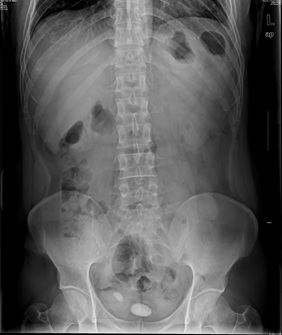

05卷-4.男,55歲,反復(fù)尿頻、尿痛、排尿困難半年

B.膀胱結(jié)石

本題答案:B

【該題針對(duì)“ X線(xiàn)-泌尿系結(jié)石 ”知識(shí)點(diǎn)進(jìn)行考核】